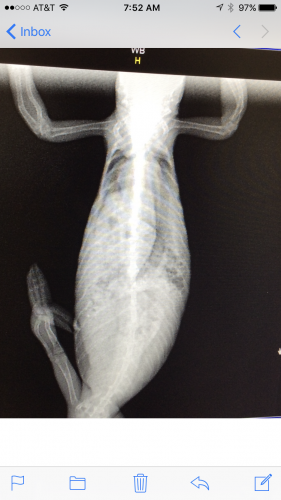

Well here's the 3 X-ray photos from yesterday of Weebo. She's 6-7 months old. Weighs 87 grams and has MBD as well as a slight respiratory infection. You can also see her starting to develop her first batch of eggs. Thought these pics were pretty cool and good for other people to see what happens to the bones. How her legs are bowed as well as clear, indicating not enough calcium within the bone structure